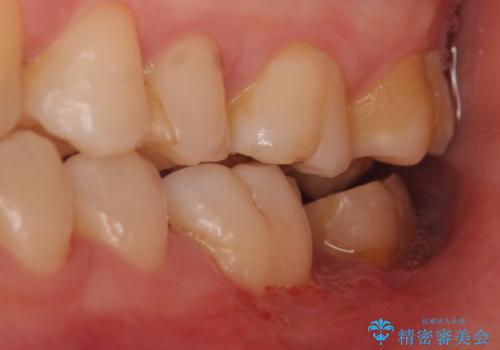

- 左下の一番奥の歯が時折激しく痛むので診て欲しいといらっしゃった方の症例です。以前に他院を受診したところ、そもそも被せ物を入れるスペースがないため抜歯しかないと言われたとのことでした。

診査の結果根尖病変を認めたため再根管治療を行った後に、被せ物を入れるスペースを作るため歯冠延長術を行いました。

オールセラミッククラウンについて

今回用いたオールセラミッククラウンはジルコニアフレームという白い素材の上にセラミックを盛っているため、審美性が非常に高いのが特徴です。

また、ジルコニアは人工ダイヤモンドの材料にも使われているほど高い強度を持っており、そのためオールセラミッククラウンは審美性だけでなく、奥歯やブリッジの補綴も可能とするクラウンです。